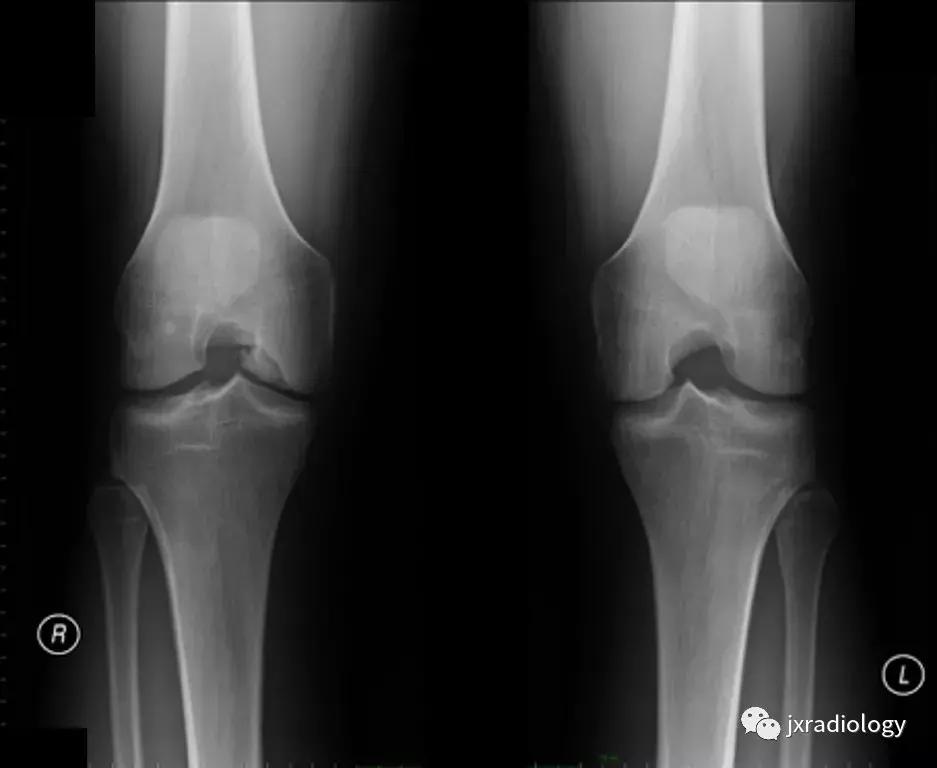

图18:剥脱性骨软骨炎(OCD)。OCD的病因学是未知的,可能是多因素的,包括损伤,血管因素,压力变化,发育差异和遗传学等。膝关节OCD最常见的部位是股骨内侧髁(75%)。这里显示了特征性的MRI表现,通常没有其它的损伤:在骨软骨碎片周围(b)有明显的小片骨髓水肿。(a,b:冠状T1-WI和冠状PD-FS-WI)。

图19:剥脱性骨软骨炎(OCD)。与图18相同的患者。X线片显示右侧股骨内侧髁见骨软骨碎片。